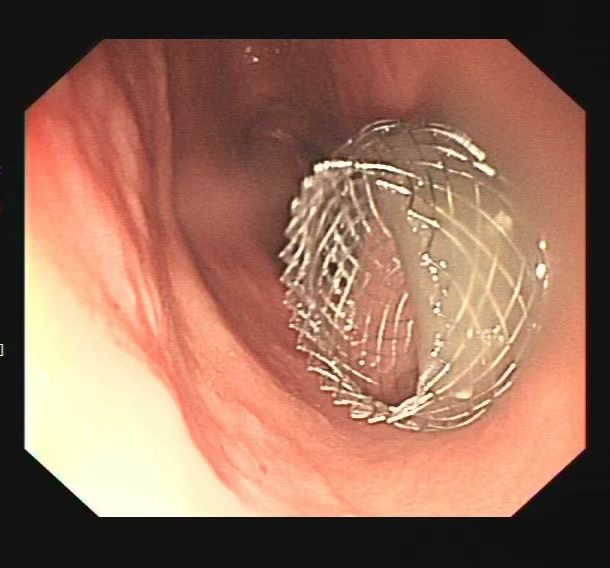

术后胃腔内支架影

在与患者及家属充分沟通后为其实施“超声内镜引导下胰腺包裹性坏死穿刺引流术+支架置入术”,术中,支架顺利释放,大量褐色囊液涌入胃内。术后复查显示,囊腔明显缩小。